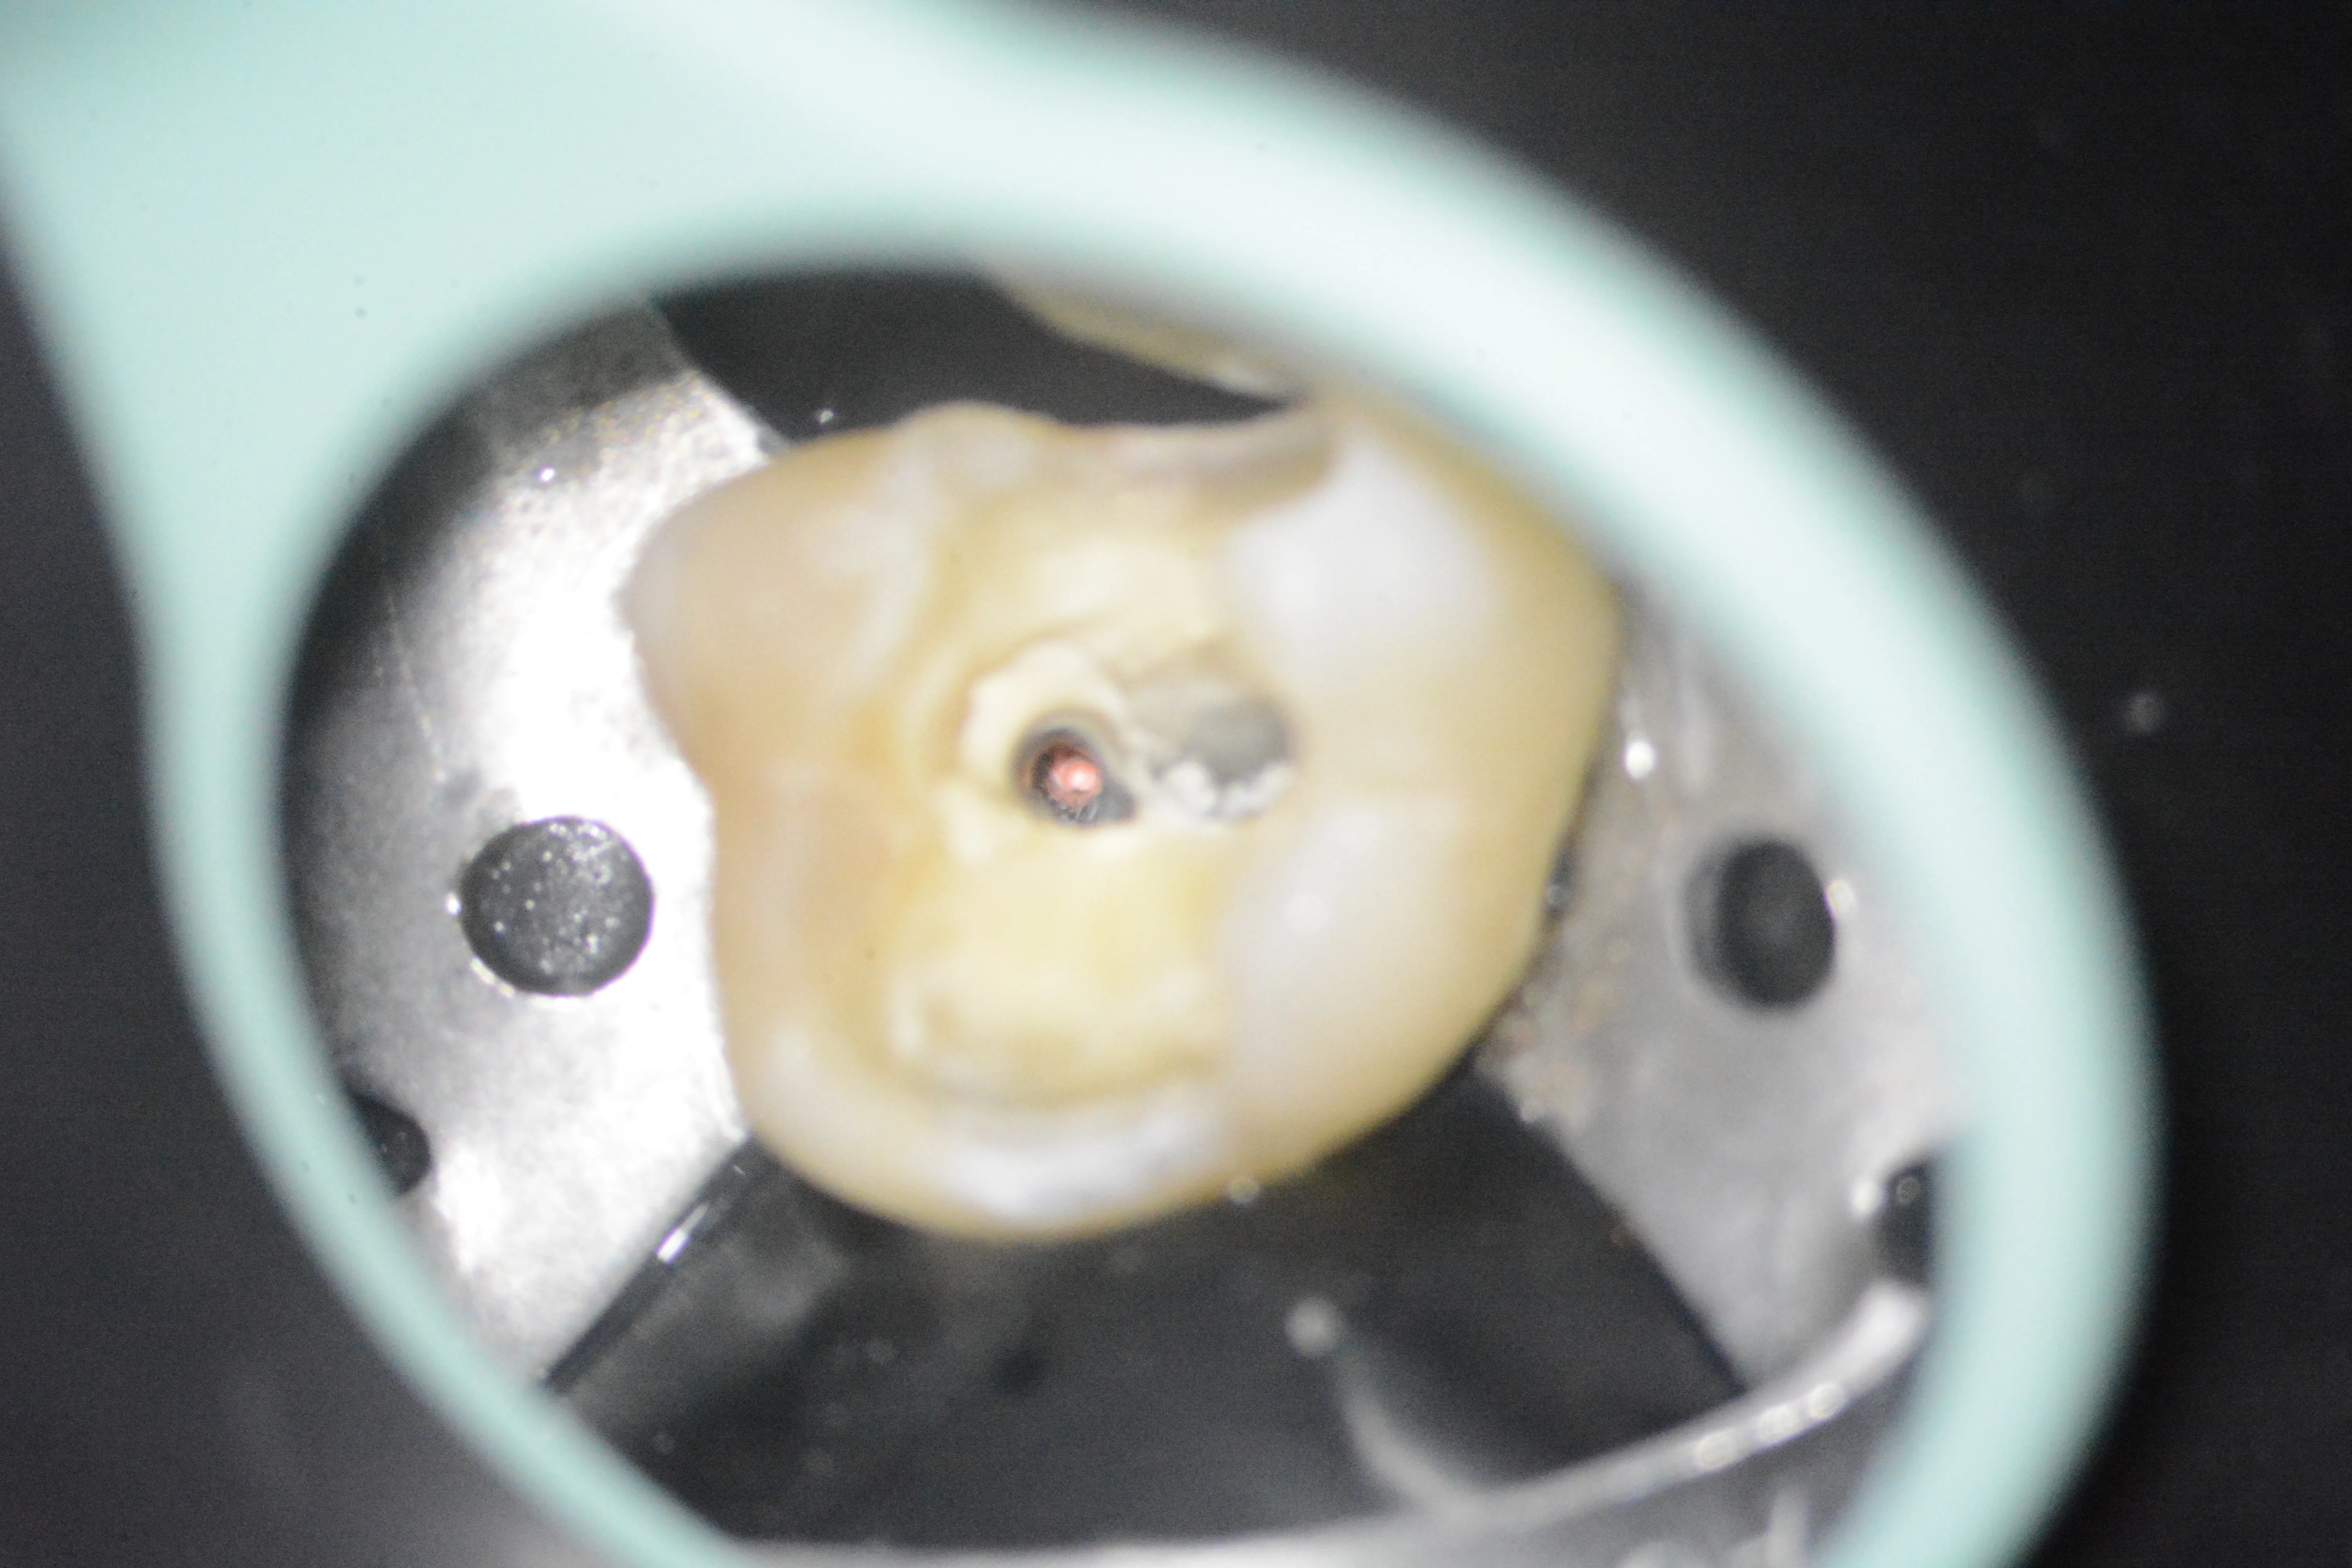

3 – Aspectul pulpei coronare